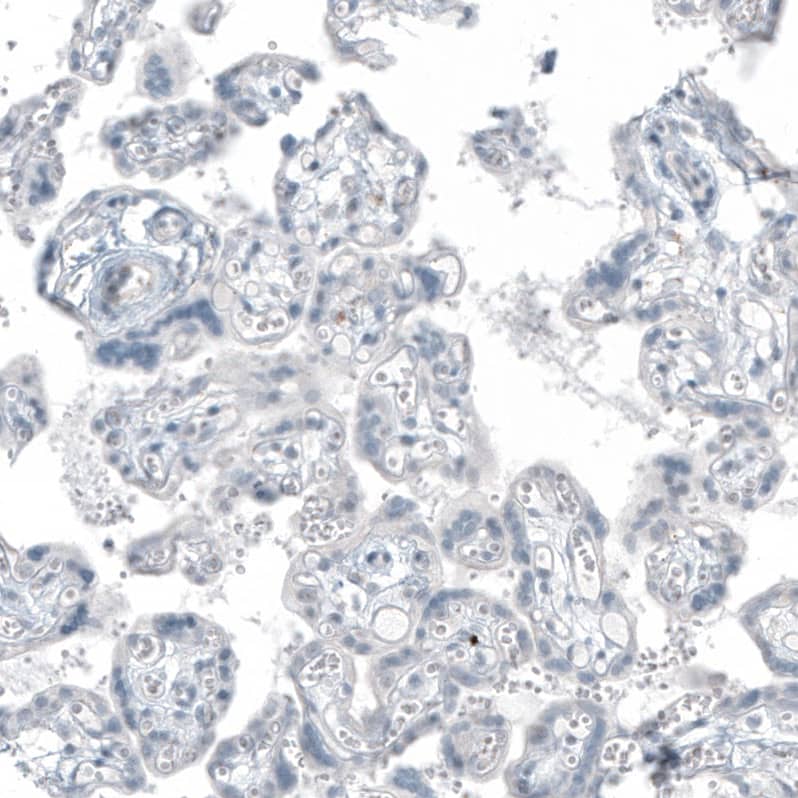

Immunohistochemistry-Paraffin: FRMD5 Antibody [NBP3-44045]

Staining of human cerebral cortex shows weak to moderate positivity in neuronal processes.Immunohistochemistry-Paraffin: FRMD5 Antibody [NBP3-44045]

Staining of human heart muscle shows moderate cytoplasmic positivity in cardiomyocytes.Applications for FRMD5 Antibody (CL9503) - Azide and BSA Free